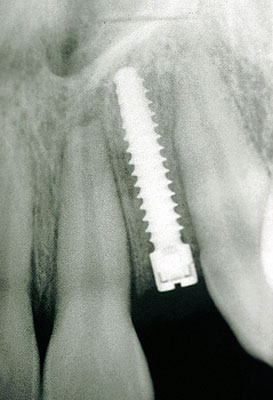

Einzelne Zähne können auch in völlig gesunden Gebissen durch Unfall oder Entzündungen verloren gehen, ebenso sind besonders die oberen seitlichen Schneidezähne häufiger nicht angelegt. Die drei Bilder zeigen den Ersatz eines nicht angelegten seitlichen oberen Schneidezahnes bei einem Jugendlichen.